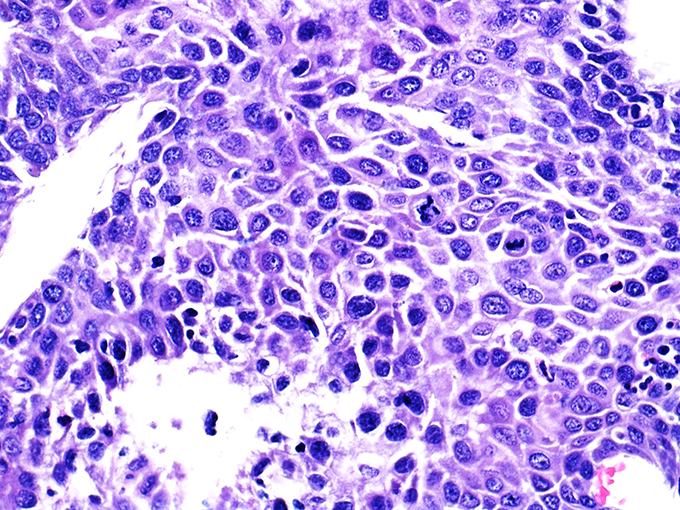

![]() Case 1

Area 1 - Soft Bx CIN 2 40x - High Power |